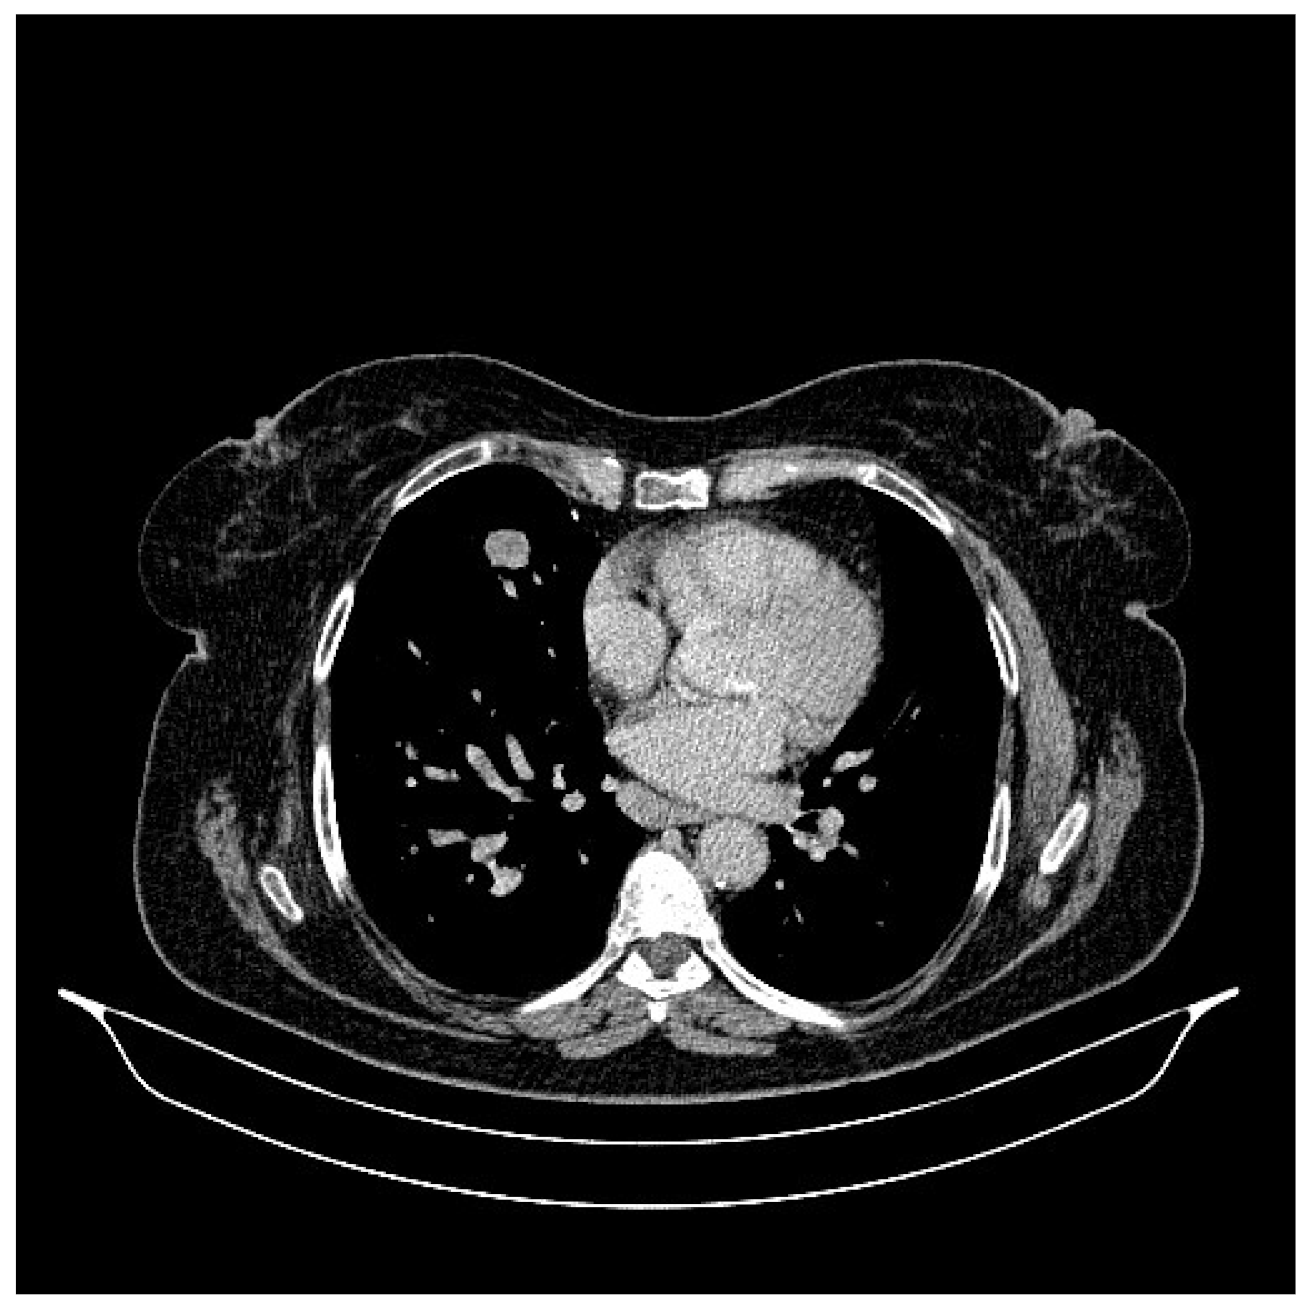

2. Case Presentation